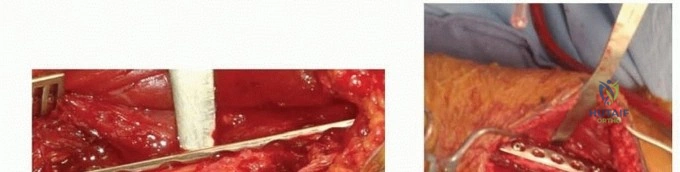

For midshaft fractures, the brachialis muscle is split longitudinally down its midline. Because the medial half is innervated by the musculocutaneous nerve and the lateral half by the radial nerve, this longitudinal split is an internervous plane that preserves the function of both segments. The split is carried down to the periosteum, and the muscle halves are elevated off the anterior humerus. The lateral half of the brachialis acts as a protective muscular cushion between the retractor (and subsequently the plate) and the radial nerve.

For distal third fractures, the exposure must transition to the interval between the brachialis and the brachioradialis. The radial nerve emerges from the posterior compartment by piercing the lateral intermuscular septum and travels distally in the cleft between the brachialis (medially) and the brachioradialis (laterally).

To safely exploit this interval, the fascia between the brachialis and brachioradialis is carefully incised. The radial nerve must be actively identified and protected. It is often easiest to identify the nerve distally where the interval is wider and trace it proximally to where it pierces the septum. Once identified, the nerve is gently mobilized and protected with vessel loops. Retraction of the nerve must be minimal and meticulous to prevent iatrogenic neuropraxia.

Once the fracture site is exposed and the hematoma evacuated, reduction is achieved using longitudinal traction, rotation, and direct manipulation with bone reduction forceps. Soft tissue interposition, particularly from the brachialis or triceps, must be cleared from the fracture ends.